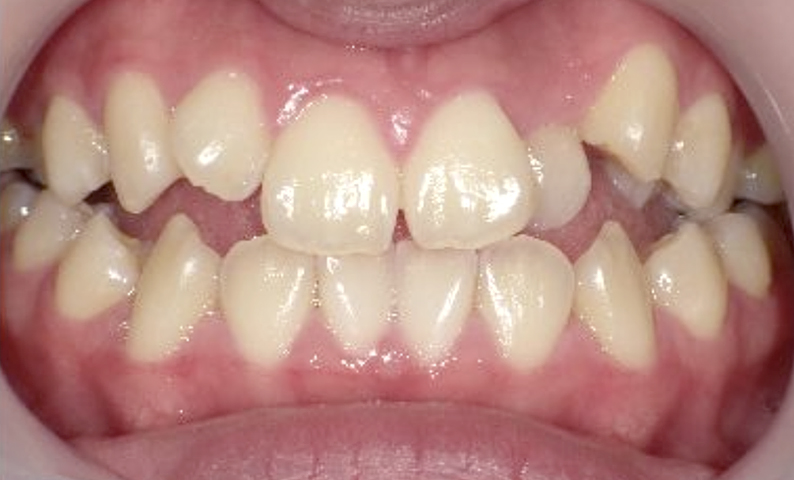

症例_003 上下顎の部分矯正

治療期間:8ヶ月金額:60万円+税女性八重歯叢生開口